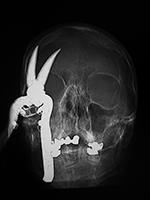

|

| 86 year-old man who fell off ladder onto pruning shears. The shear handle went through the floor of his right orbit and right maxillary sinus. His globe was intact. AP and lateral scout CT images. |

Axial CT image after surgical repair of the right orbital floor with titanium mesh. |

Coronal CT image after surgical repair of the right orbital floor with titanium mesh. |